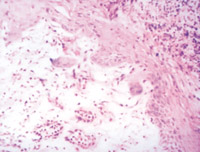

5-2-1 傷后第1天,表皮凝固性壞死,真皮淺層膠原纖維變性  HE×100